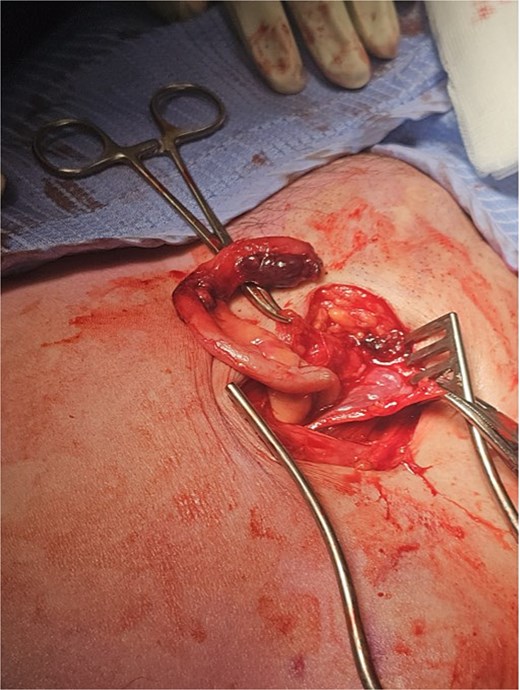

The working radiological diagnosis was an incarcerated Amyand’s hernia. However on examination, the lump appeared to be below the inguinal ligament more in keeping with a femoral hernia. Therefore under general anaesthesia, a high approach was taken. This revealed a femoral hernia under the inguinal ligament. Rectus sheath was opened transversely. A preperitoneal reduction was unsuccessful so peritoneum was opened in the right iliac fossa. This revealed an appendix incarcerated in the femoral hernia. The hernia was reduced revealing a grossly inflamed appendiceal tip (Fig. 3). An open appendicectomy was done, the hernia was closed with an intraperitoneal 1–0 Ethibond suture before closing the peritoneum, fascia, and skin.

Histology confirmed marked ischaemia of the appendix consistent with a mechanical veno-occlusive aetiology.